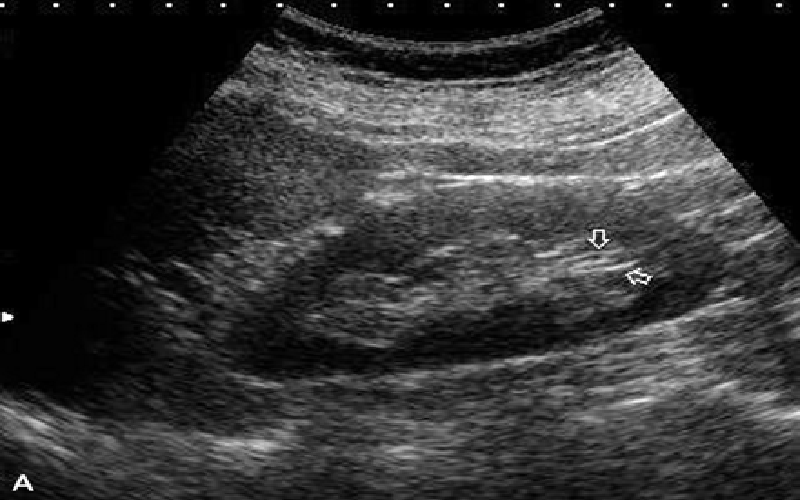

• Xuất hiện hình ảnh màu trắng trên ảnh siêu âm, có bóng đen là dấu hiệu thận đã bị sỏi thận.

Siêu âm thận để làm gì? Lợi ích khi siêu âm thận 2 Thận nhỏ là một trong các dấu hiệu của viêm thận mãn tính.